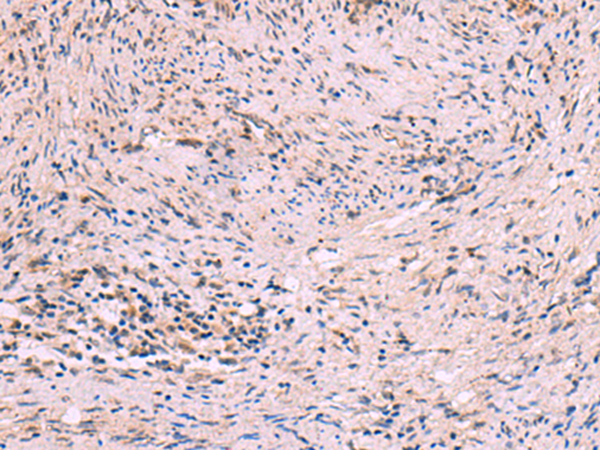

IHC positive control: |

Human cervical cancer |

IHC Recommend dilution: |

10-50 |